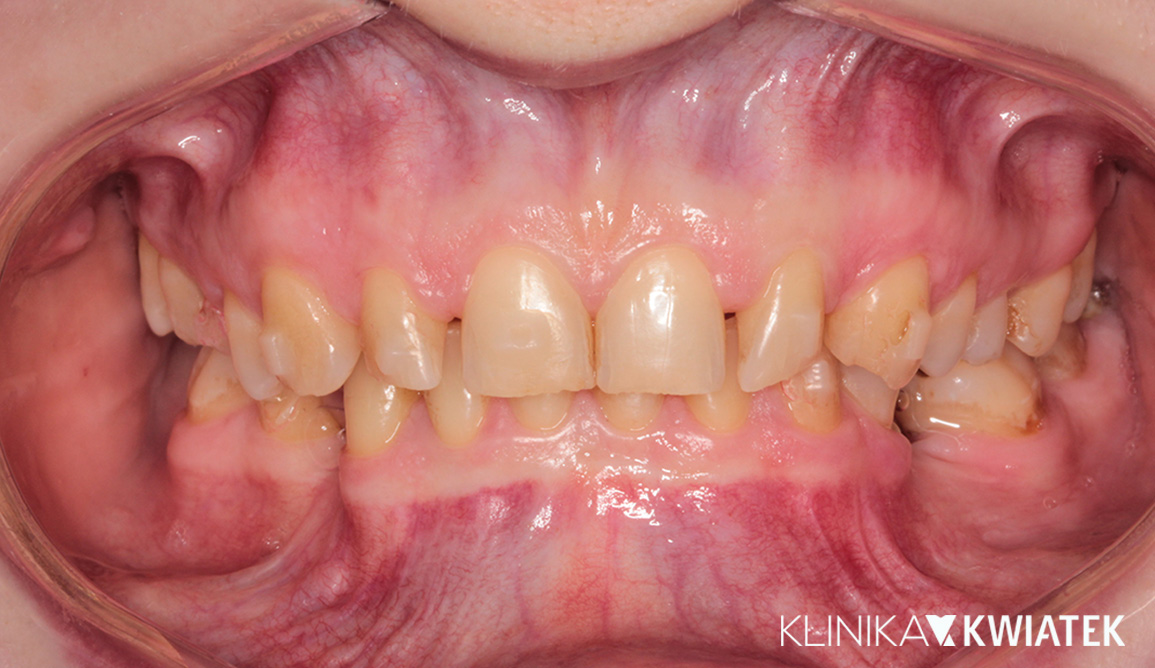

Najpierw zdrowie. Potem ortodoncja - stabilne warunki jamy ustnej jako fundament metamorfozy

Pacjent przez kilka lat pozostawał pod opieką kliniki, realizując etapowe leczenie zachowawcze i profilaktyczne, którego celem było pełne ustabilizowanie stanu jamy ustnej. Po zakończeniu leczenia próchnicy, ekstrakcjach zębów mądrości oraz zabiegach profilaktycznych – świadomie i w odpowiednim momencie – podjął decyzję o leczeniu ortodontycznym. Efektem kompleksowej terapii jest uśmiech będący zwieńczeniem lat świadomych decyzji, precyzyjnego planowania i konsekwentnego leczenia.